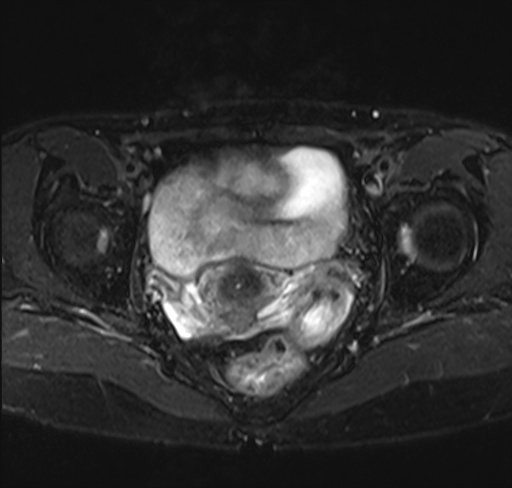

手术后CT照

2020年5月8日,主刀医师牛院长在全麻下为她进行卵巢癌全切手术。谁也不知道开刀后会是一个怎样的情况,大家保持精神高度集中,小心翼翼的划开肚皮直至卵巢位置,一点点的将癌组织与正常组织分离开,经过两个小时手术成功了。

当我醒过来的时候,我很庆幸自己还活着,也许上天听到我的心声,几天后医生拿着化验单来到我身边对我说,卵巢癌细胞消失了,一个都没有。我迟迟没缓过神,我不敢相信这是真的,这简直就像做梦一样。我询问医生,这是不是意味着我是个健康的人。医生说理论上是可以这么认为,并且表示我很幸运,这种情况出现就像一个奇迹,再过段时间只要消除肺部的癌细胞,我就可以“健康”回到原来的生活中。